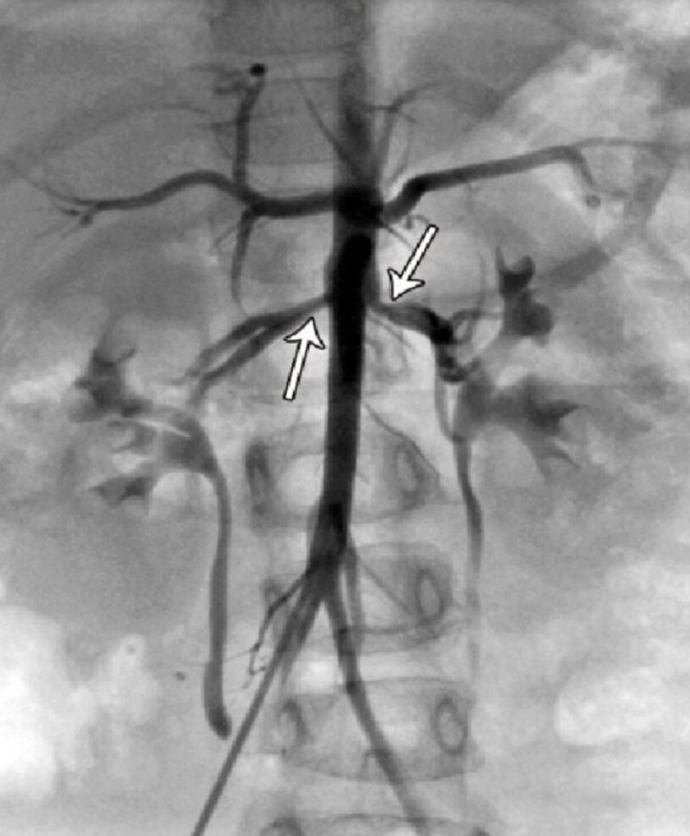

RAS Imaging: Catheter Angiography

Gold standard

Catheter + dye to visualize arteries